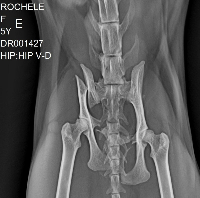

Ela sofreu um acidente ainda desconhecido, mas muito provavelmente ela foi atropelada. Ela tem 2 fraturas na pelve e escoriações pelo corpo. Vai precisar de cirurgia para estabilizar e no momento eu não tenho condições 😭😭

Os orçamentos para a cirurgia giram em torno dos 5 mil reais.